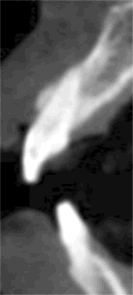

A 43 year-old lady has lost #7 and 8 due to caries for ~ 2 year. It appears that the ridge is wide (Fig.1). To place implants in ideal position, cone beam CT is planned. Models are mounted (Fig.2); diagnostic wax-up is finished (Fig.3). Drill sleeves (arrowheads in Fig.4; 10 mm long, 2.2 mm in diameter; Straumann) are placed lingual to the incisal (I) edges of the neighboring teeth. The position of drill sleeves is confirmed by CT: between the incisal edge and the cingulum (Fig.5). The cross sections at #7, 8 and 9 are shown in Fig. 6, 7 and 8, respectively. However, the long axis of the sleeve (S) or the natural tooth #9 is not aligned with that of the alveolar ridge. This orientation is good from prosthetic viewpoint, but we cannot place a long or wide implant. The lateral view of the three-dimensional image shows that the long axis of the crown (C) of #9 is not in line with that of its root/ridge (R, Fig.9). It appears that the trajectory of an implant should be not decided by wax-up, but should be adjusted to accommodate the morphology of the alveolar ridge. In all, the drill sleeve (S) should be moved and tilted more labially to place the longest and largest implant.